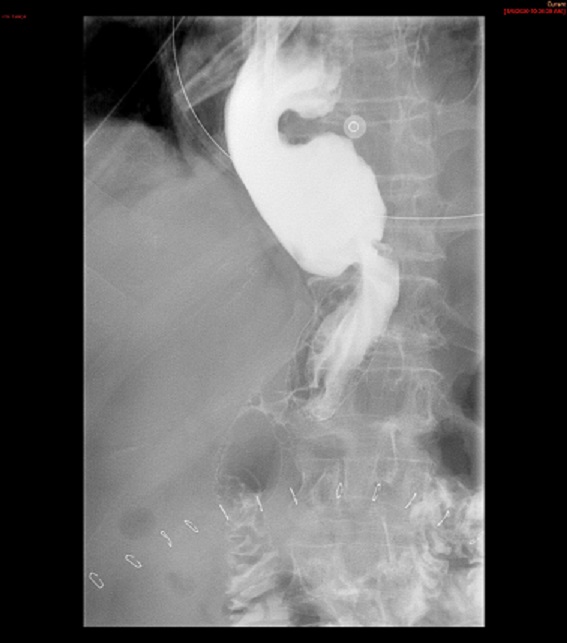

- Method—Thoracic:

- With the patient standing upright, have them turn into a left posterior oblique position.

- Instruct the patient that you will be handing them a cup containing a small amount of water and effevescent crystals and that they should drink it as quickly ask possible.

- As soon as the patietn has finished the water, exchange the empty cup for a cup of thick barium.

- Ask the patient to drink two (2) sips of thick barium. The patient does not need to drink this quickly.

- After the patient has begun drinking, take images of the upper and lower esophagus distended and coated with barium

(key image 5)

(key image 6)

(key image 7).

- Thoracic images are obtained in the upright RPO and LPO projections after the adminstration of bubbly barium (EZ Gas followed by thick barium).

- The goal of these images is to see the thoracic esophagus distended and coated with barium. This may not be possible with one image and make take several to accomplish.